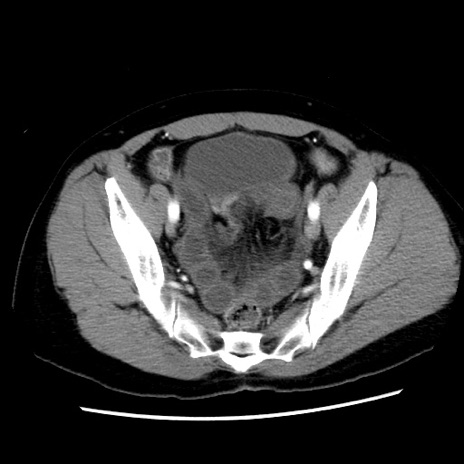

矢状断像